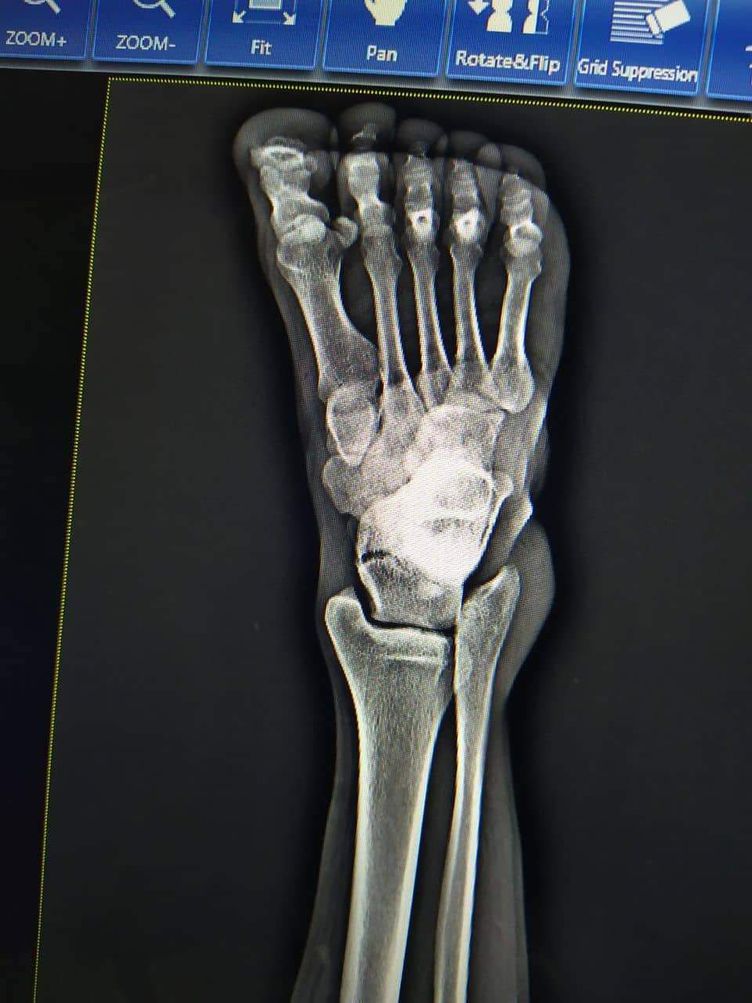

Talar body fracture. Immediate first aid treatment is to apply a well-padded splint around the back of the foot and leg from the toe to the upper calf to immobilize the limb and protect it. Elevating the foot above the level of the heart helps to minimize swelling and pain

And then consult orthopedic for surgery.